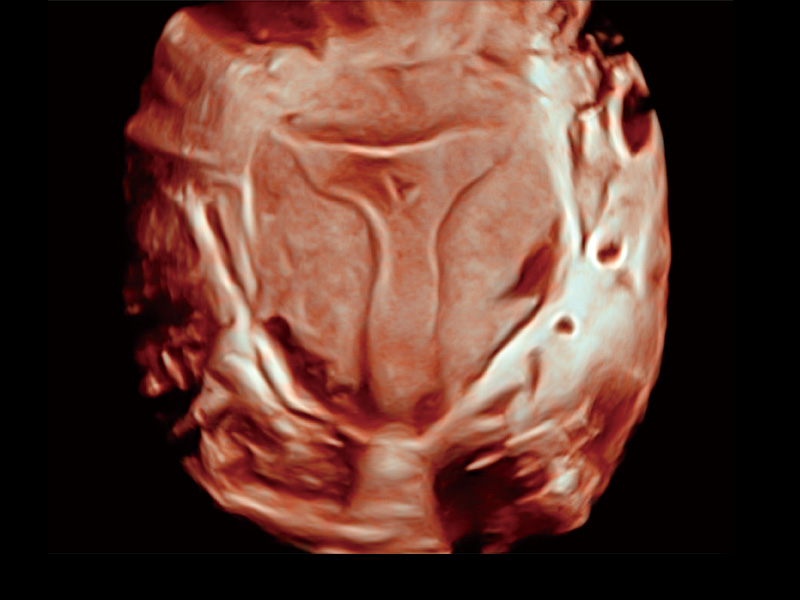

单角子宫